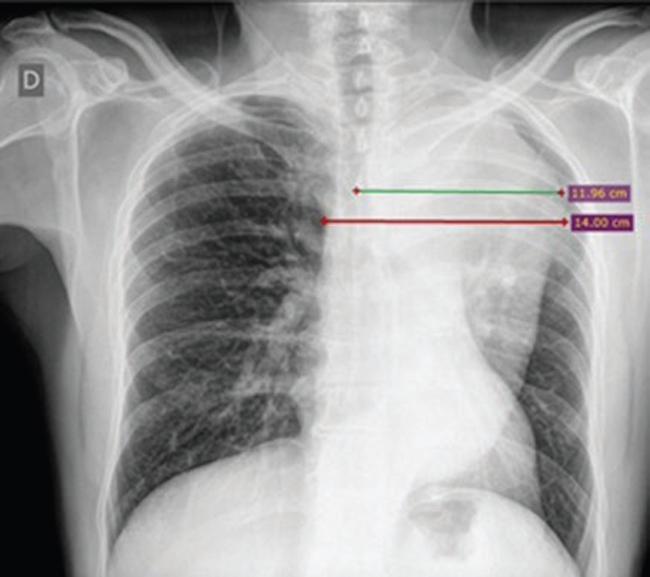

Ancho mediastínico máximo: definido por la distancia máxima del borde lateral derecho al borde lateral izquierdo del mediastino superior a nivel del botón aórtico (Figs. 1 y 2).

Ancho mediastínico izquierdo: definido por la distan-cia máxima tomada desde la línea media de la tráquea al borde lateral izquierdo del mediastino a nivel del cayado aórtico (Figs. 1 y 2).